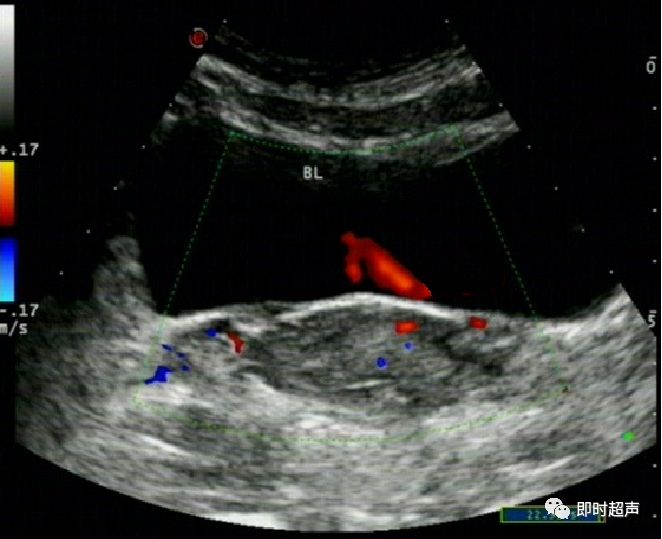

输尿管*尿喷**现象

(膀胱三角区、膀胱后壁两侧可见输尿管开口,排尿时可见输尿管口*尿喷**现象,尿流自后方斜向对侧前方,有断续光点移动。CDFI:显示尿流呈红色或橘红色。)